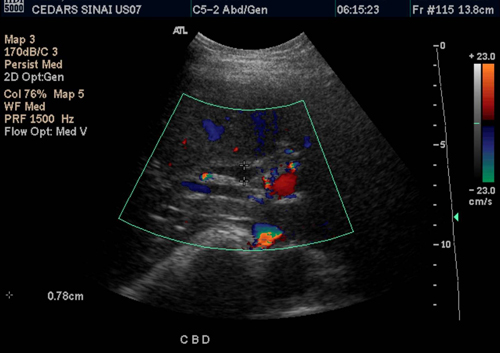

The day of the ultrasound arrived, and Aarti was met with a team of compassionate healthcare professionals who guided her through the process with care and understanding. As she lay on the examination table, the cool gel applied to her abdomen, she felt a mix of apprehension and relief. The procedure was quick and painless, and soon after, Aarti was presented with a detailed report.

The results were eye-opening. The ultrasound revealed a minor but significant condition that required medical attention. With this newfound knowledge, Aarti was able to consult with her doctor and develop a treatment plan that addressed the issue before it could escalate into something more serious. The relief she felt was immense, knowing she had taken a proactive step in safeguarding her health.

Aarti's story is a testament to the power of early detection and intervention. Whole abdomen ultrasounds offer a non-invasive, efficient way to gain insights into one's health, allowing for timely and informed decisions. For women like Aarti, who often prioritize the needs of others, it is a vital tool in reclaiming their well-being.